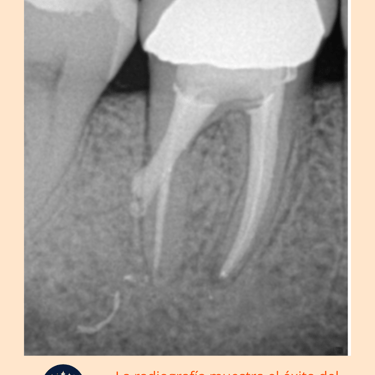

Relleno y Sellado: El conducto radicular se rellena y se sella para completar el tratamiento endodóntico.

Restauración: Se coloca una corona o restauración para proteger y fortalecer el diente.

Resultados esperados: El sellado adecuado de la perforación permite salvar el diente y prevenir complicaciones futuras.